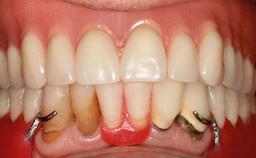

Improving an Existing Implant-supported Denture in an Alzheimer Patient with Bipolar Affective Disorder with Moderate Depression and Dementia

An 83-year-old man presented together with his caregiver at the dental department of the Medical University of Innsbruck, Austria with complaints of swelling in the right maxillary canine area and loss of retention of his 5-years-old mandibular denture. The patient had a significant medical history (20 years) of bipolar affective disorder with moderate depression (F 31.3) and dementia in Alzheimer’s disease (F 00.2). The patient had been in ambulant psychiatric therapy for his depressive illness for the past 20 years. He lived alone and had no children; his sister assisted with daily living. She reported that the patient exhibited compulsive hoarding behavior. In the previous two months, she had noted increasing disorientation and vertigo in the patient. She therefore accompanied him for a medical consultation at the Department of Psychiatry and Psychotherapy of the Medical University of Innsbruck. He was released home after a 6-week inpatient stay.

Infection at Implant Site None Chronic Acute

Periodontal Status History of periodontitis or genetic predisposition